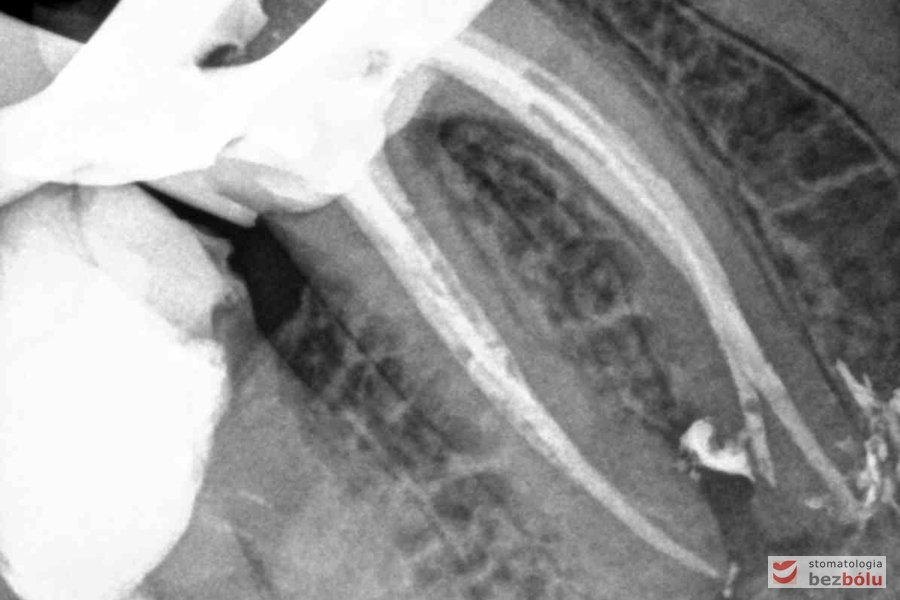

Radiowizjografia - jedynka górna prawa z niedopełnionym kanałem korzeniowym

Radiowizjografia – jedynka górna prawa z niedopełnionym kanałem korzeniowym